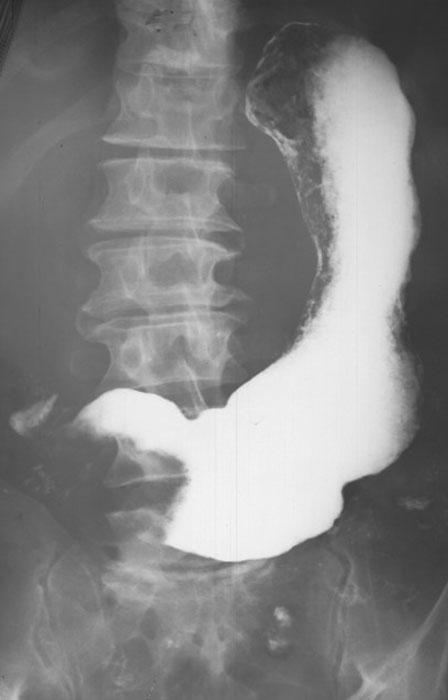

What may be seen on chest X-ray with a large hiatus hernia?

Retrocardiac soft-tissue mass with an air-fluid level.

How do you differentiate the esophagus from the stomach on a barium study?

Esophagus = smooth; stomach = rugal folds.

What is the key landmark to identify in a hiatus hernia?

Diaphragm.